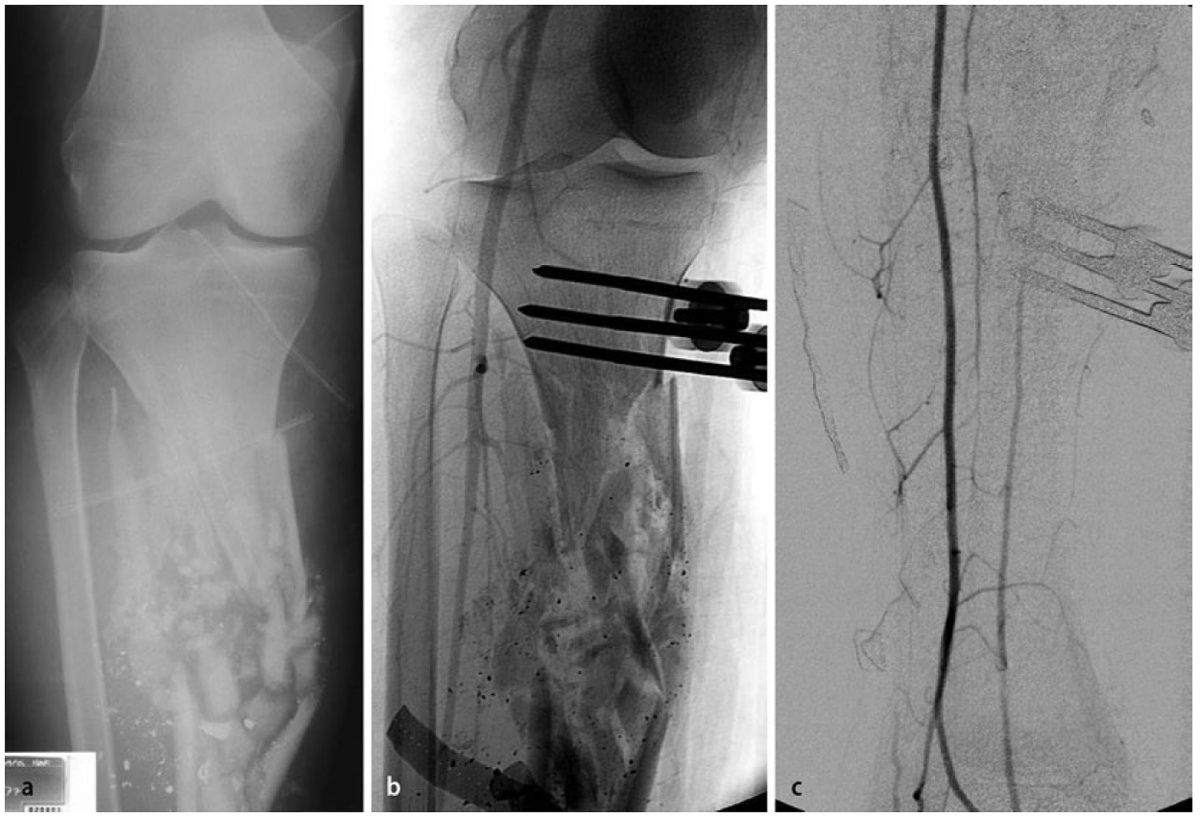

Es zeigt sich das typische Bild einer Schussfraktur nach Niedrigenergieverletzung. a seitlicher Strahlengang,

b a. p. Strahlengang

Beim Auftreffen des Projektils im Rahmen von Niedrigenergieverletzungen auf Knochengewebe entsteht meist eine typische, einfache Fraktur (Abbildung 2). Hochenergieverletzungen des Knochens münden in eine multifragmentäre Situation, bei der ein Großteil der Projektilenergie an den Knochen abgegeben wird. Insbesondere lange Röhrenknochen können, da sie wie eine starre, spröde flüssigkeitsgefüllte Röhre agieren, durch Projektile mit hoher Energie explosionsartig zerstört werden (Abbildung. 3).